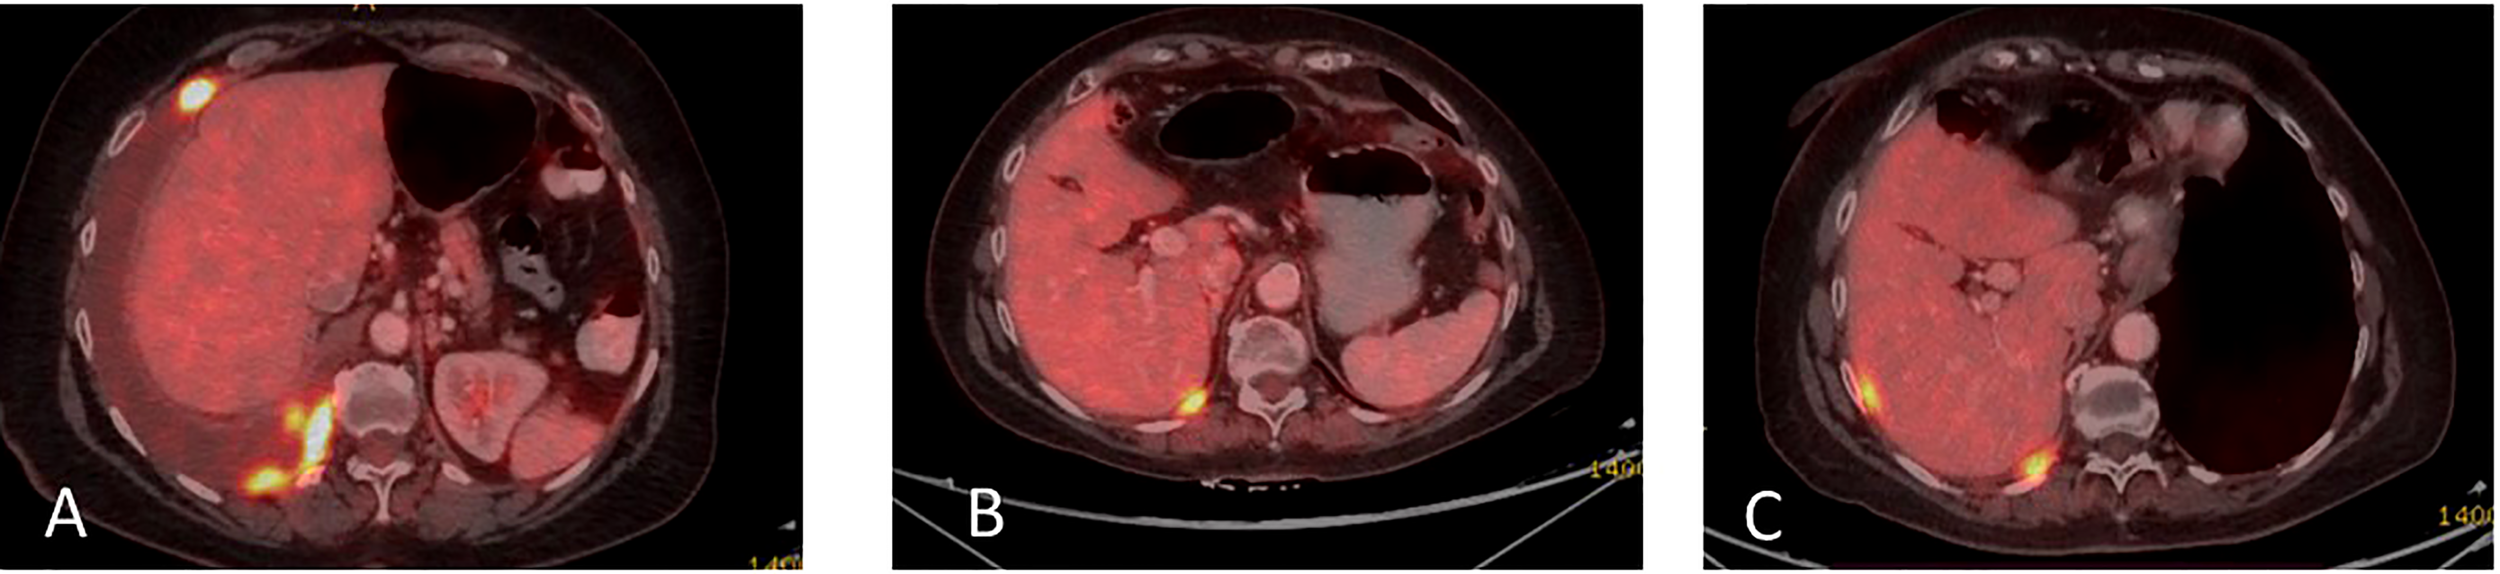

In December 2020, multiple liver metastases were identified on PET-CT (Figure 3A). At this time, another comprehensive genomic test (Tempus) was performed which identified further progression of EGFR- L858R (61.1%) and L833V mutations (63.4%), as well as the development of additional findings such as CEP85L-ROS1 fusion and MET amplification (6 copies), as shown in Table 1. Treatment with osimertinib (80mg daily) was then attempted, but the disease continued progressing (Figure 3B). At this time, crizotinib (250 mg bid) was added to the current regimen. Following 2-months of combination therapy, the liver mass substantially decreased in its size and numbers (Figure 3C). Dose reduction of crizotinib (250 mg once daily) was required following an ischemic stroke. In October 2021, the patient passed away due to further disease progression.

Figure 3

(A) Coronal section, superimposed PET-CT scan, December 2020. Four years after the first presentation of stage 3B NSCLC, the right lung shows a significant reduction in FDG-18 uptake and decreased tumor size, with only a scar, indicating the lung’s complete response to treatment. However, status-post left hepatectomy, there is increased FDG-18 uptake in the right lobe of the liver, consistent with multifocal right hepatic metastatic disease. (B) Two months later, February 2021, there is further progression in size, number, and metabolic activity of metastases throughout the right lobe of the liver, indicating more aggressive disease. There remains no evidence of recurrent or residual disease in the lung. (C) Non-contrast, axial CT scan from April 2021 shows interval regression in size and number of liver masses. The white spots are sutures from the surgery to remove the left hepatic lobe (status-post left hepatectomy).